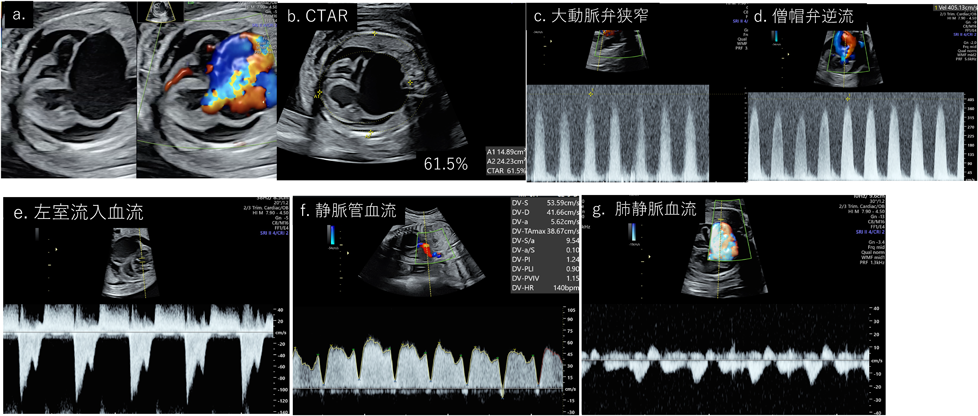

重症大動脈弁狭窄(critical aortic stenosis: CAS)は大動脈弁狭窄により,著明な僧帽弁逆流を呈し,左房の拡張を来す.左室の後負荷の上昇により,左室の収縮能と拡張能異常を来し,心不全や胎児水腫に至る可能性の高い疾患(Fig. 10a)である.超音波所見としては著明な心拡大を来し(Fig. 10b),大動脈弁順行性通過血流速度の上昇(Fig. 10c),僧帽弁逆流(mitral regurgitation: MR; Fig. 10d)を認める.MRが3.14 m/s以上であれば,胎児治療の大動脈弁バルーン拡張術を行い生後の2心室循環に移行できる可能性が高いという報告があり29),CASの予後指標の一つである.またMRまたは大動脈流出路最大収縮期圧較差20 mmHg以上が本邦の胎児治療の適応基準にもなっている.拡張障害として,filling timeが短縮するため,症状が進行すると1層性のinflow patternとなる.本症例でCVPSを計算すると,皮下浮腫と心嚢液の貯留による胎児水腫で−2点,CTAR=61.5%で−2点,全収縮期のMRで−2点,静脈管の逆流で−2点,正常な臍帯動脈で2点のため,合計2点であり,予後はかなり厳しいという予測になる(Fig. 10a–f).また肺静脈ドプラーは左房圧を反映していると考えられており,a波の逆流やs波とd波の間のpulsationを考慮すると,左房圧が上昇していることが推測される(Fig. 10g).

Pediatric Cardiology and Cardiac Surgery 40(2): 103-112 (2024)

Fig. 10 重症大動脈弁狭窄

CTAR, cardiothoracic ration